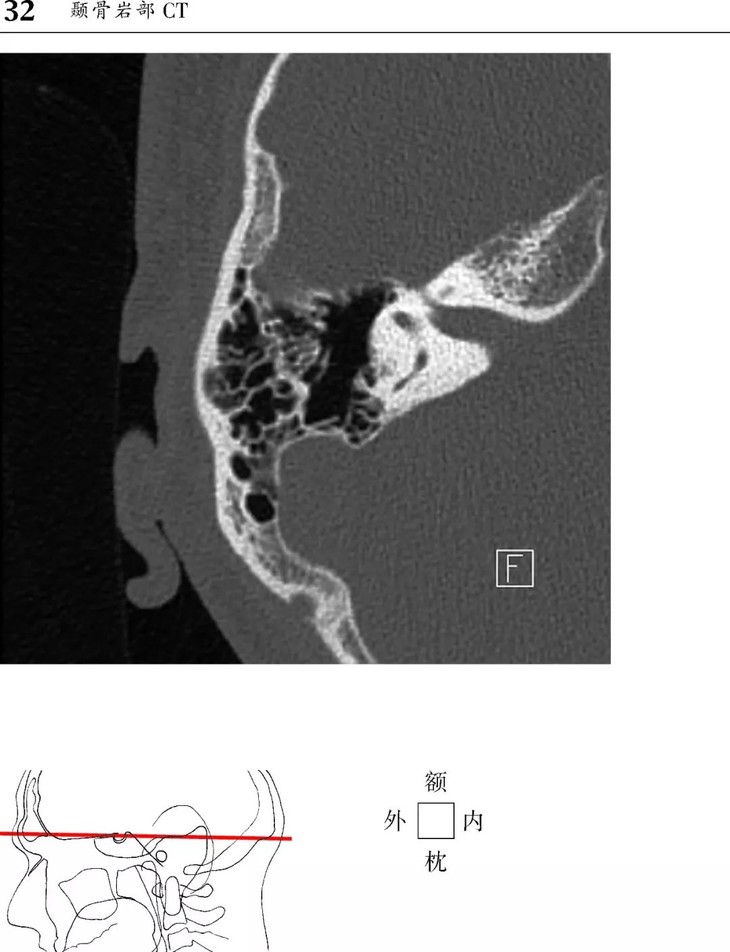

1、头部CT图像新增轴位和冠状位颞骨图像。

本书为断层解剖图谱,包括头颈部断层解剖,还包括脑部血管造影术,每一层面都包括精确的断层解剖和对应的彩色插图,左边页面为CT/MR图像,右边页面为对应的彩色手绘解剖示意图,便于学习和记忆!

1、版面采用教学式设计,2页为一个单元,左边页面为CT/MR图像,右边页面为对应的彩色手绘解剖示意图,并一一注明了解剖部位。

2、几百幅高清的CT/MR图片,对解剖结构显示更加清晰,其中许多图片都是采用最新的设备扫描的,如3.0T MRI,64层CT。